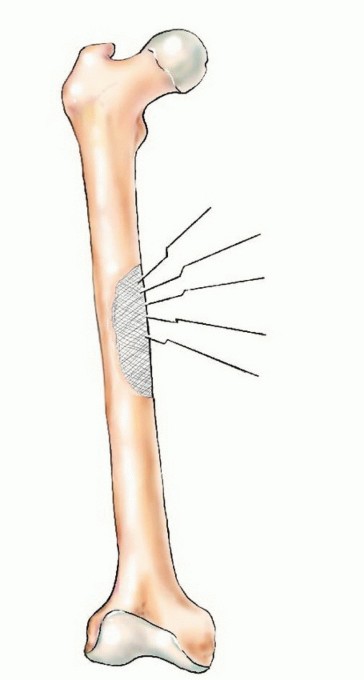

الأشعة السينية والتصوير المقطعي المحوسب CT

يجب إجراء صور الأشعة السينية العادية والتصوير المقطعي المحوسب (CT) للموقع المصاب، بالإضافة إلى صور الأشعة السينية العادية لأي موقع إضافي يبلغ فيه المريض عن ألم في المفصل أو العظم. ستحدد النتائج المجمعة لهذه الدراسات مدى تدمير العظام وامتداد الأنسجة الرخوة.

إذا كانت النقيلة قيد الفحص تقع في عظم طويل، فيجب أيضًا إجراء صور أشعة سينية ذات جودة معقولة لكامل امتداد العظم لاستبعاد وجود نقائل إضافية؛ لأن هذه البيانات حاسمة للتخطيط الجراحي. قد تتسبب النقائل التي لم تُكتشف في كسور مرضية عند تحمل الوزن بعد الجراحة وتتطلب جراحة واسعة لإصلاحها.